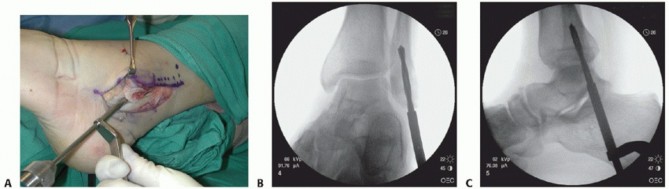

| 4. ## Modified Technique Using a Large-Diameter Drill Bit (as Described by Robert B. Anderson, MD) | |||

| Chronically dislocated peroneal tendons may create a new pocket and even gliding surface on the lateral fibula (TECH FIG 7). | |||

| Protect the dislocated tendons and adjacent soft tissues from the drill bit. | |||

| From the distal fibular tip, introduce progressively larger diameter drill bits to weaken the distal fibula and ream away the distal fibular cancellous bone (TECH FIG 8). | |||

| Although simple impaction of the posterior fibula to deepen the groove is possible at this point, we prefer to first weaken the cortex with a microsagittal saw as described for the traditional fibular groove-deepening | |||

| procedure (TECH FIG 9A). | |||

| To protect the smooth surface on the posterior fibula, a tamp can be placed longitudinally in the groove and impacted so as to avoid disruption of the smooth gliding surface for the peroneal tendons (TECH FIG 9B). | |||

| The peroneal tendons should remain reduced without manually restraining them (TECH FIG 10A). If not, then deepen the groove further with a larger diameter drill bit and perform further impaction of the posterior fibular surface. | |||

| Reattach the SPR to the posterolateral fibular margin via drill holes. | |||

| Be sure the peroneal tendons glide well without restriction in the deeper fibular groove (TECH FIG 10B). Standard closure | |||

| * TECH FIG 8 • A. Drill bit introduced to decancellate the distal fibula. B,C. Fluoroscopic confirmation of proper drill bit position in distal fibula. B. AP view. C. Lateral view. | |||